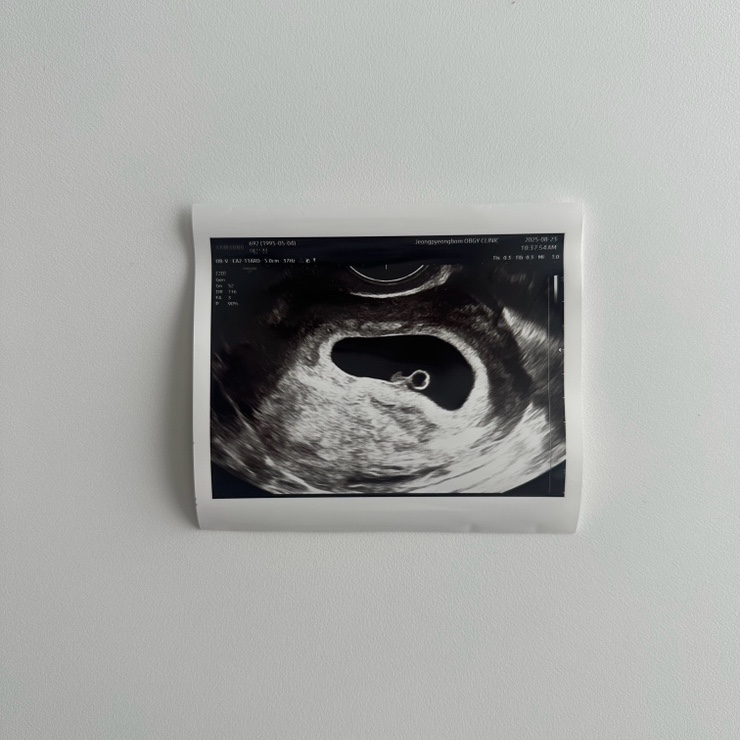

주수일기 6-7주 차 : 심장소리, 산전검사, 입덧약 부작용, 분만병원 지정, 조리원 예약

수주일기 6-7주차, 심장 소리도 듣고 오고 입덧으로 고생한 주, 일상 스타트 ! 6주차 6주차가 되면 심장소...